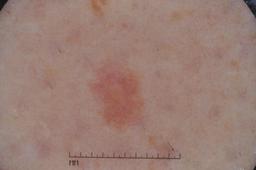

ISIC-DICM-17K (ISIC Dermoscopic Images and Clinical Metadata 17K) is a curated and balanced dataset derived from the International Skin Imaging Collaboration (ISIC) Archive Gallery. It comprises 17,060 dermoscopic images and clinical metadata (8,530 melanoma and 8,530 non-melanoma classes).

For more details, please follow the project’s GitHub repository: https://github.com/mmu-dermatology-research/isic-dicm-17k

This dataset was used in this study and benchmark to explore the effectiveness of multimodal learning for skin lesion classification:

S. Ahammed, X. Cui, W. Lu and M. H. Yap, "Skin Lesion Classification using Dermoscopic Images and Clinical Metadata: Insights from Multimodal Models," 2025 IEEE/CVF Conference on Computer Vision and Pattern Recognition Workshops (CVPRW), Nashville, TN, USA, 2025, pp. 222-230, DOI: 10.1109/CVPRW67362.2025.00027